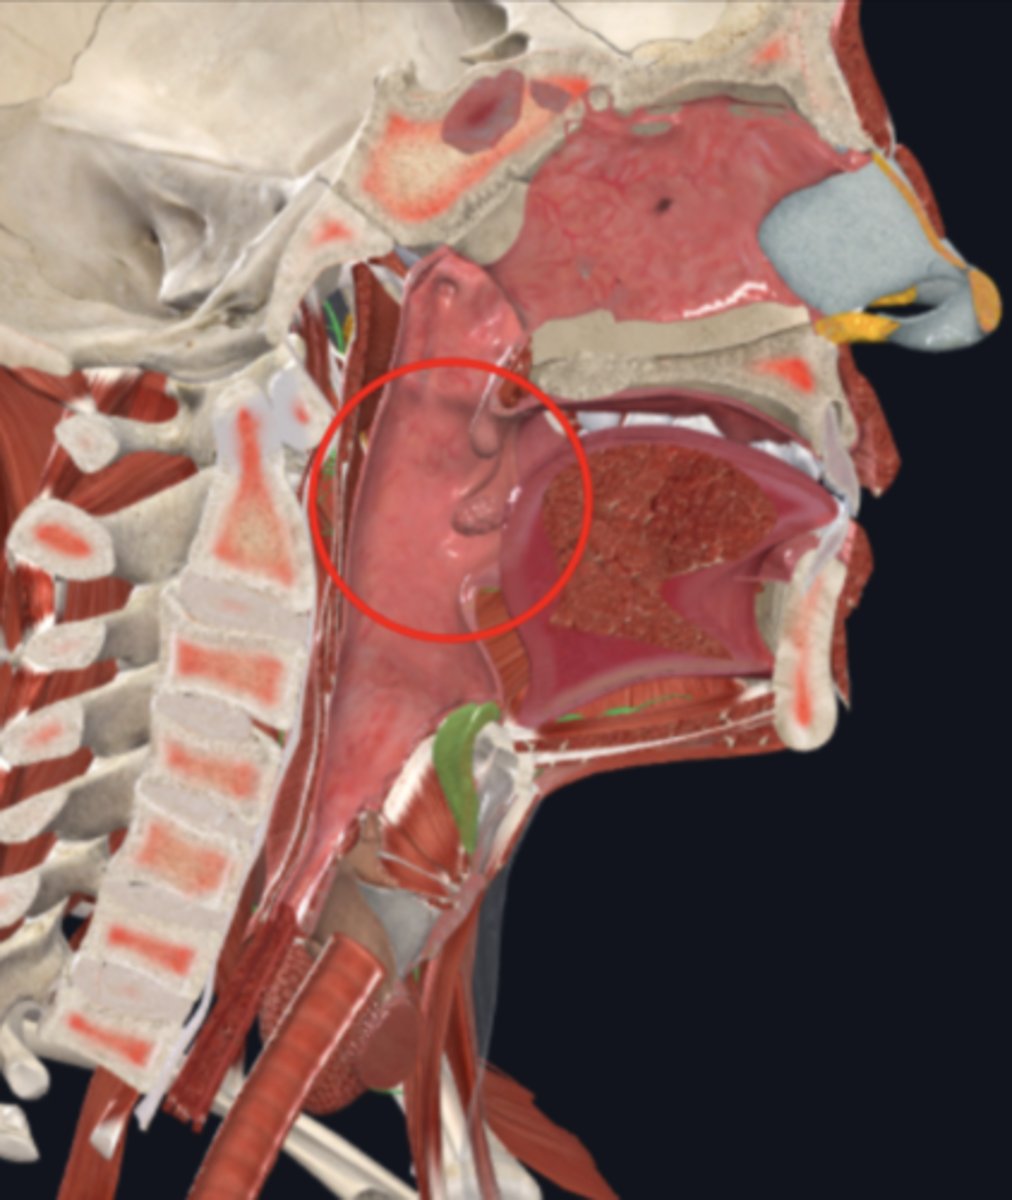

nasopharynx

name the circled region

oropharynx

name the circled region

laryngopharynx

name the circled region